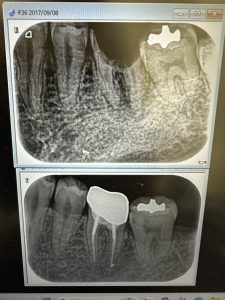

根管治療経過、良く治ってきてる💪

マメに殺菌、消毒、長さ測りネチッコくやれば誰でも上手くいきます